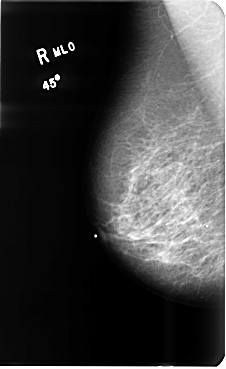

B_3512_1.RIGHT_MLO

RIGHT_MLO LINES 4792 PIXELS_PER_LINE 2936 BITS_PER_PIXEL 12 RESOLUTION 50 NON_OVERLAY